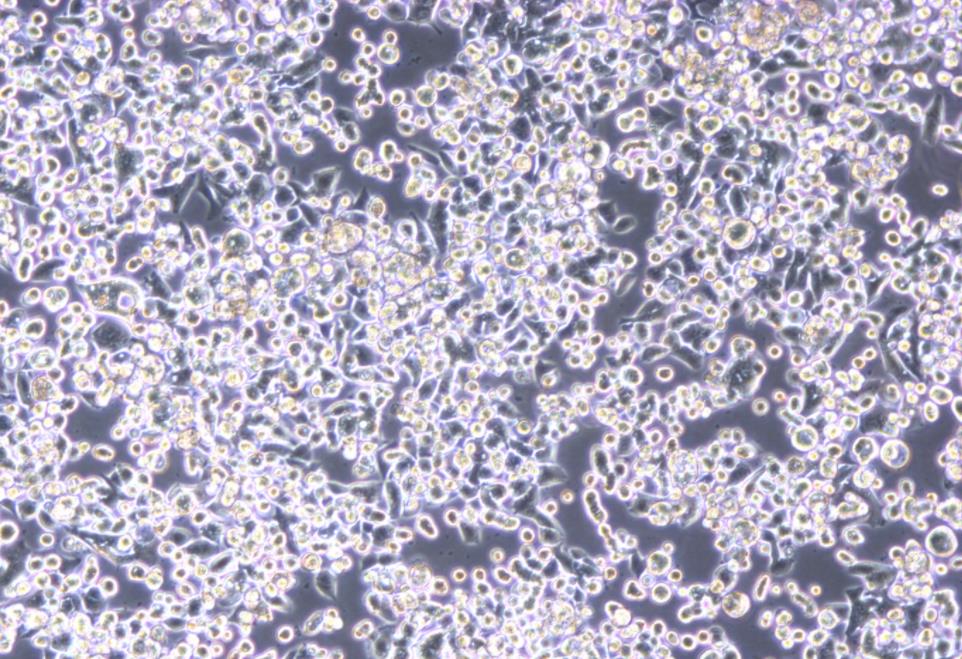

形态 |

上皮细胞样 |

生长特征 |

贴壁,悬浮混合生长 |

KATO III 细胞具有球形形态,是从一名 55 岁的亚洲男性胃癌患者的胸腔积液中体外建立的 |